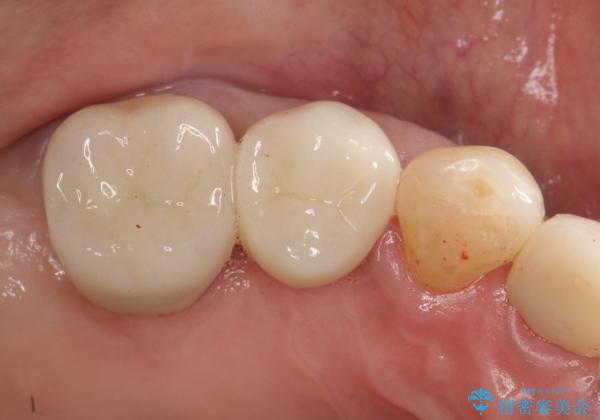

歯周病の進行した歯の抜歯。オールセラミッククラウン

最後方臼歯は根尖部まで歯周病が進行しており、抜歯を行なったのち、残存歯は歯周外科を行なったのちオールセラミッククラウンにて修復治療を行なっています。

歯周外科を行う事により歯周ポケットを除去し予知性の高い治療を行うことができますが治療期間がかかります。